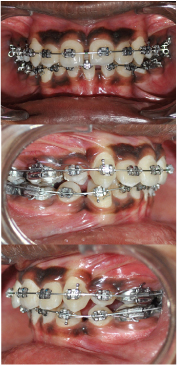

The case was treated using “Hybrid Segmental Mechanics” with extraction of all four 1st premolars with initial segmental retraction of maxillary canines and mandibular right canine using 0.017x0.025" TMA (Titanium, Molybdenum, Aluminum), ‘T-loop’ retraction spring [1,2] [Table/Fig-4a&b]. After segmented retraction of canine, leveling and alignment was carried out using continuous arch sliding mechanics using 0.016" Ni-Ti [Table/Fig-5a-c] and 0.019x0.025" Ni-Ti [Table/Fig-6a-c]. Residual Space closure was achieved using class II elastics [Table/Fig-7a&b]. In mandibular arch, right first molar was protracted to attain class I molar relationship. Finishing and detailing was carried out after closing all spaces. Most of the treatment objectives were met with the treatment, with good intraoral and facial results [Table/Fig-8a-c,9a-e,10a&b,11]. Pretreatment & post-treatment superimposition showed significant dento-alveolar change and good vertical control [Table/Fig-12a&b].

Canine Retraction with ‘T’ loop.